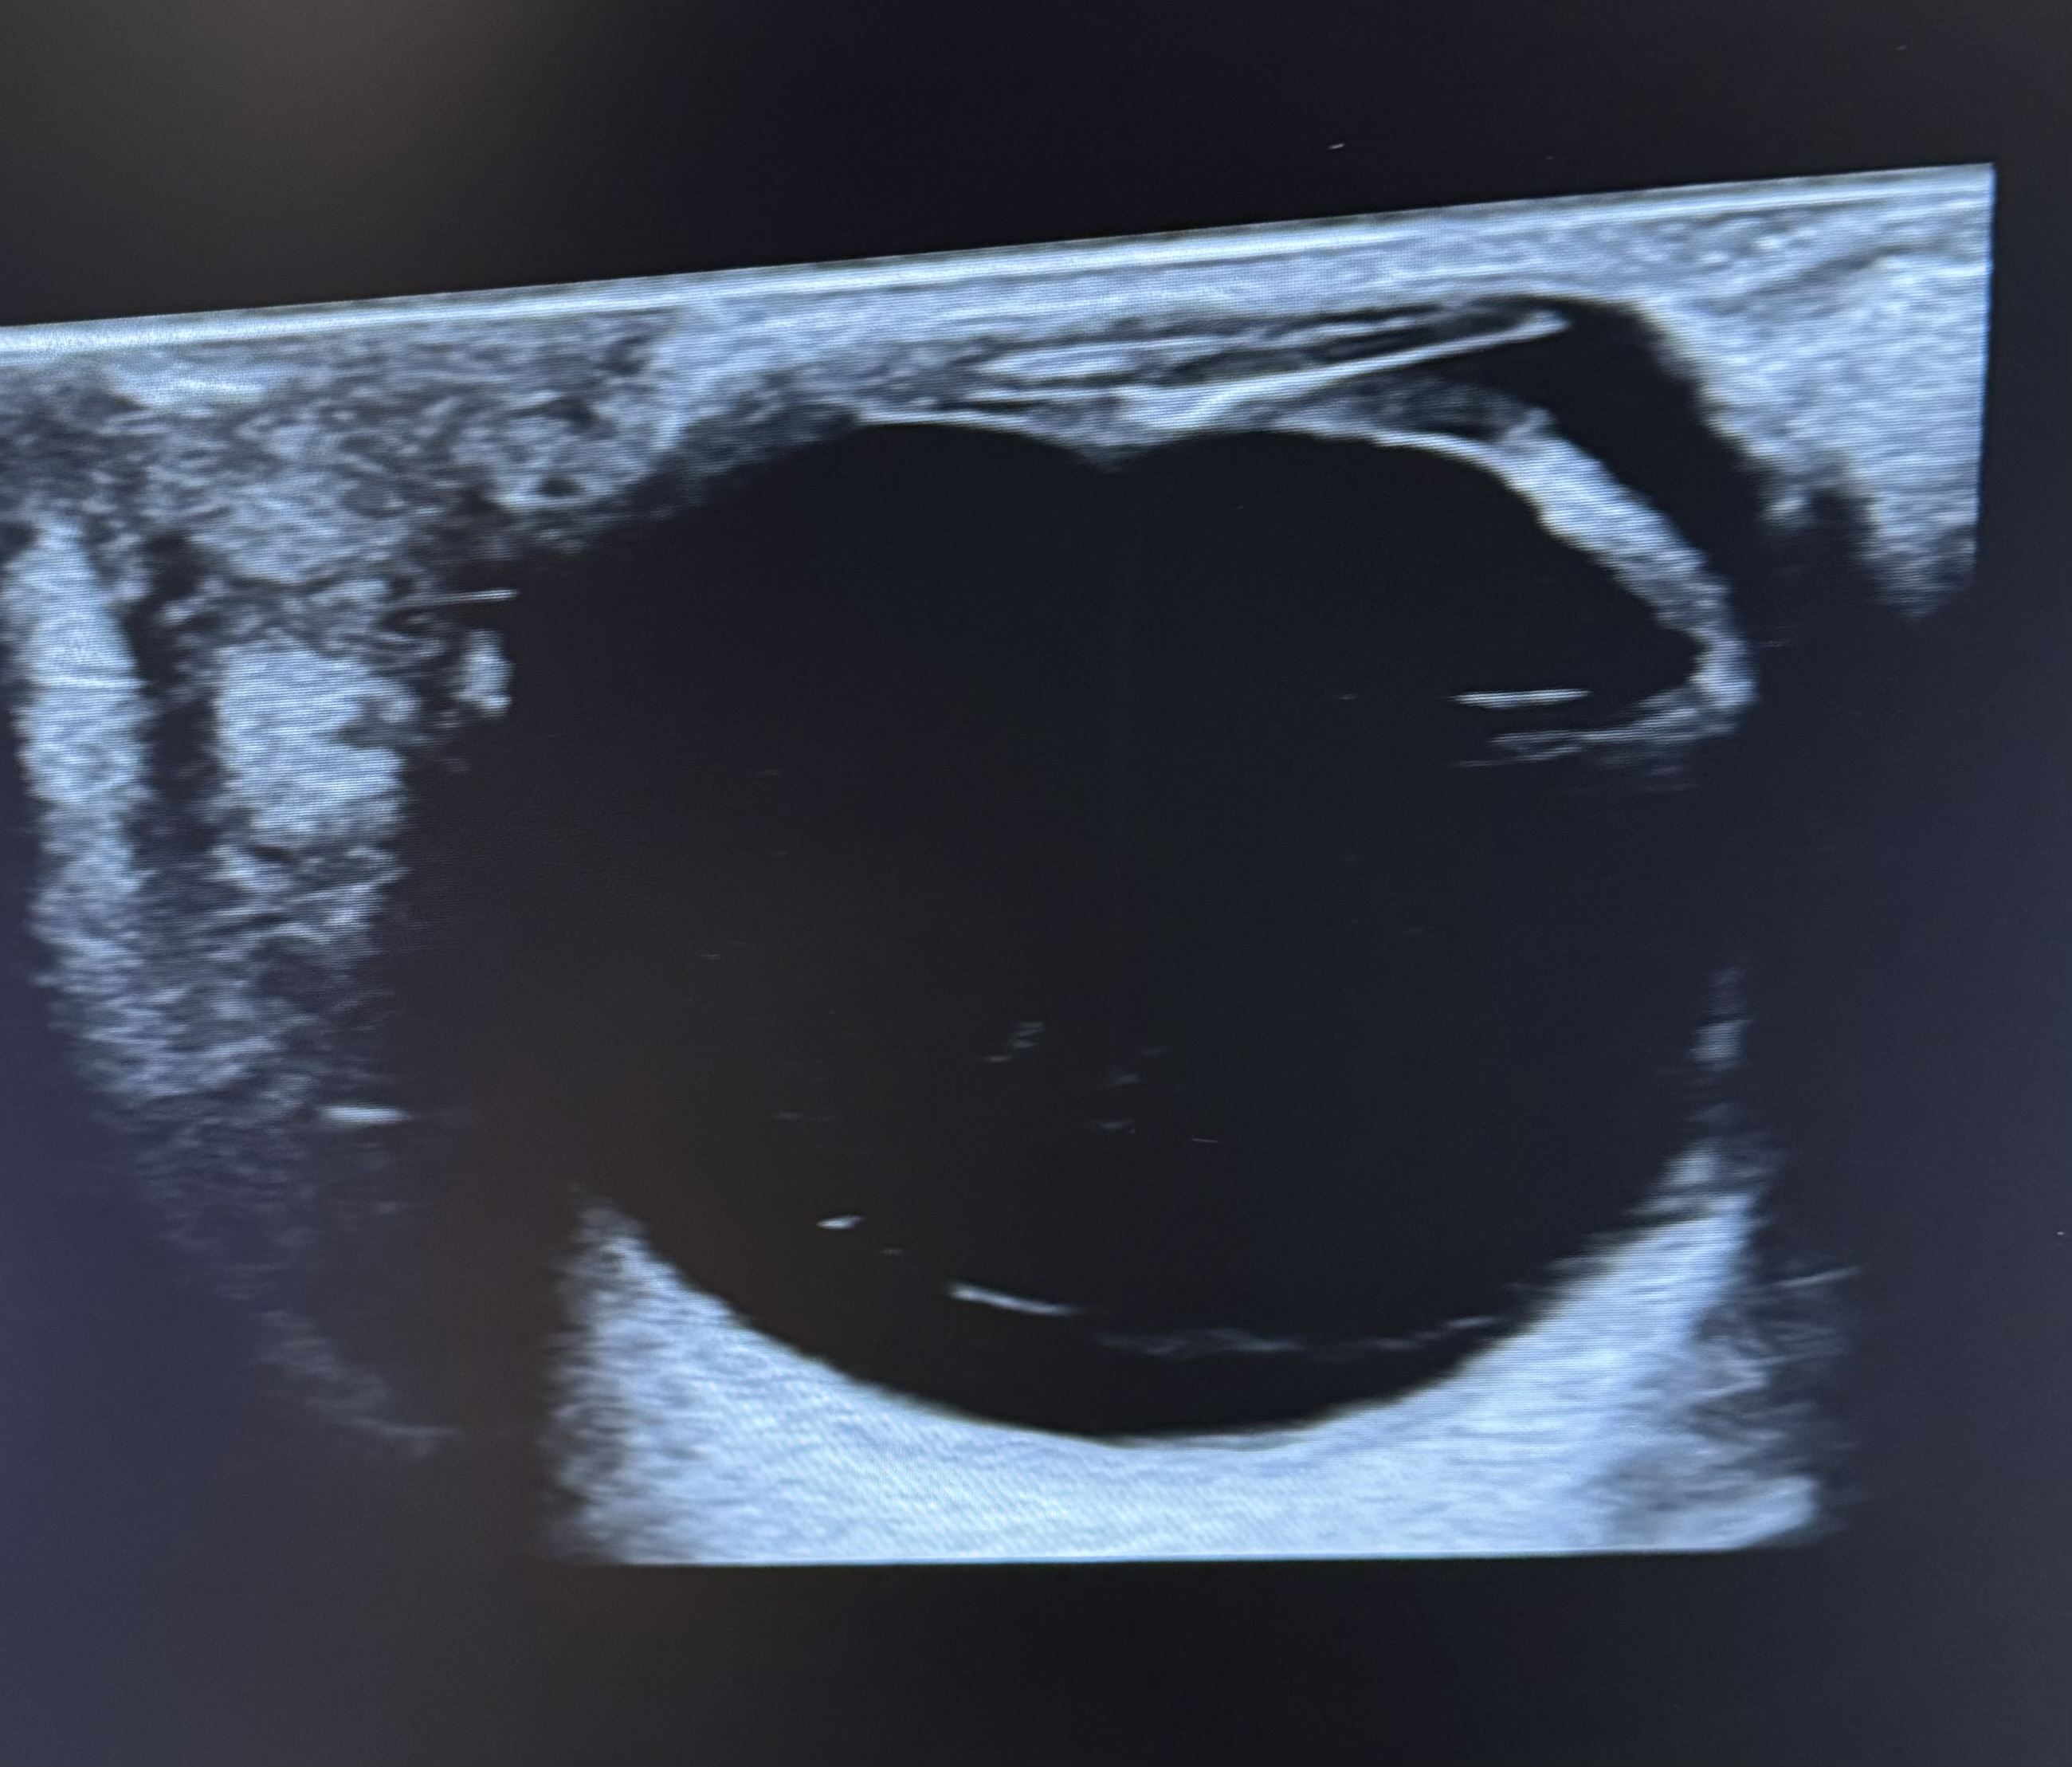

Hallazgos ecográficos

Ante la sospecha de desprendimiento de vítreo posterior (DVP) se realiza ecografía clínica. En la zona posterior del humor vítreo, anterior a la papila, se objetiva una línea fina, hiperecogénica y cóncava que hace sospechar DVP.